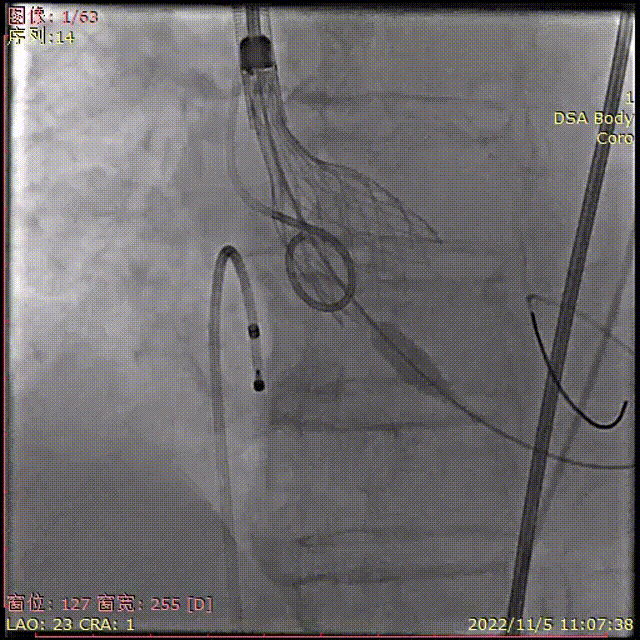

术中影像

主动脉根部造影

导丝顺利跨瓣

TaurusElite输送器顺利过弓

瓣膜初始定位

瓣膜稳定释放到工作位,无位移

工作位多角度评估

瓣膜完全释放